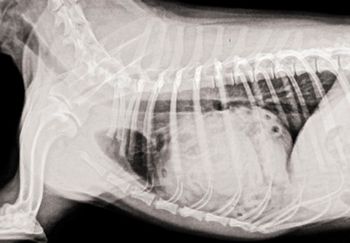

The cat, which had history of heartworm disease, presented with rear leg lameness.